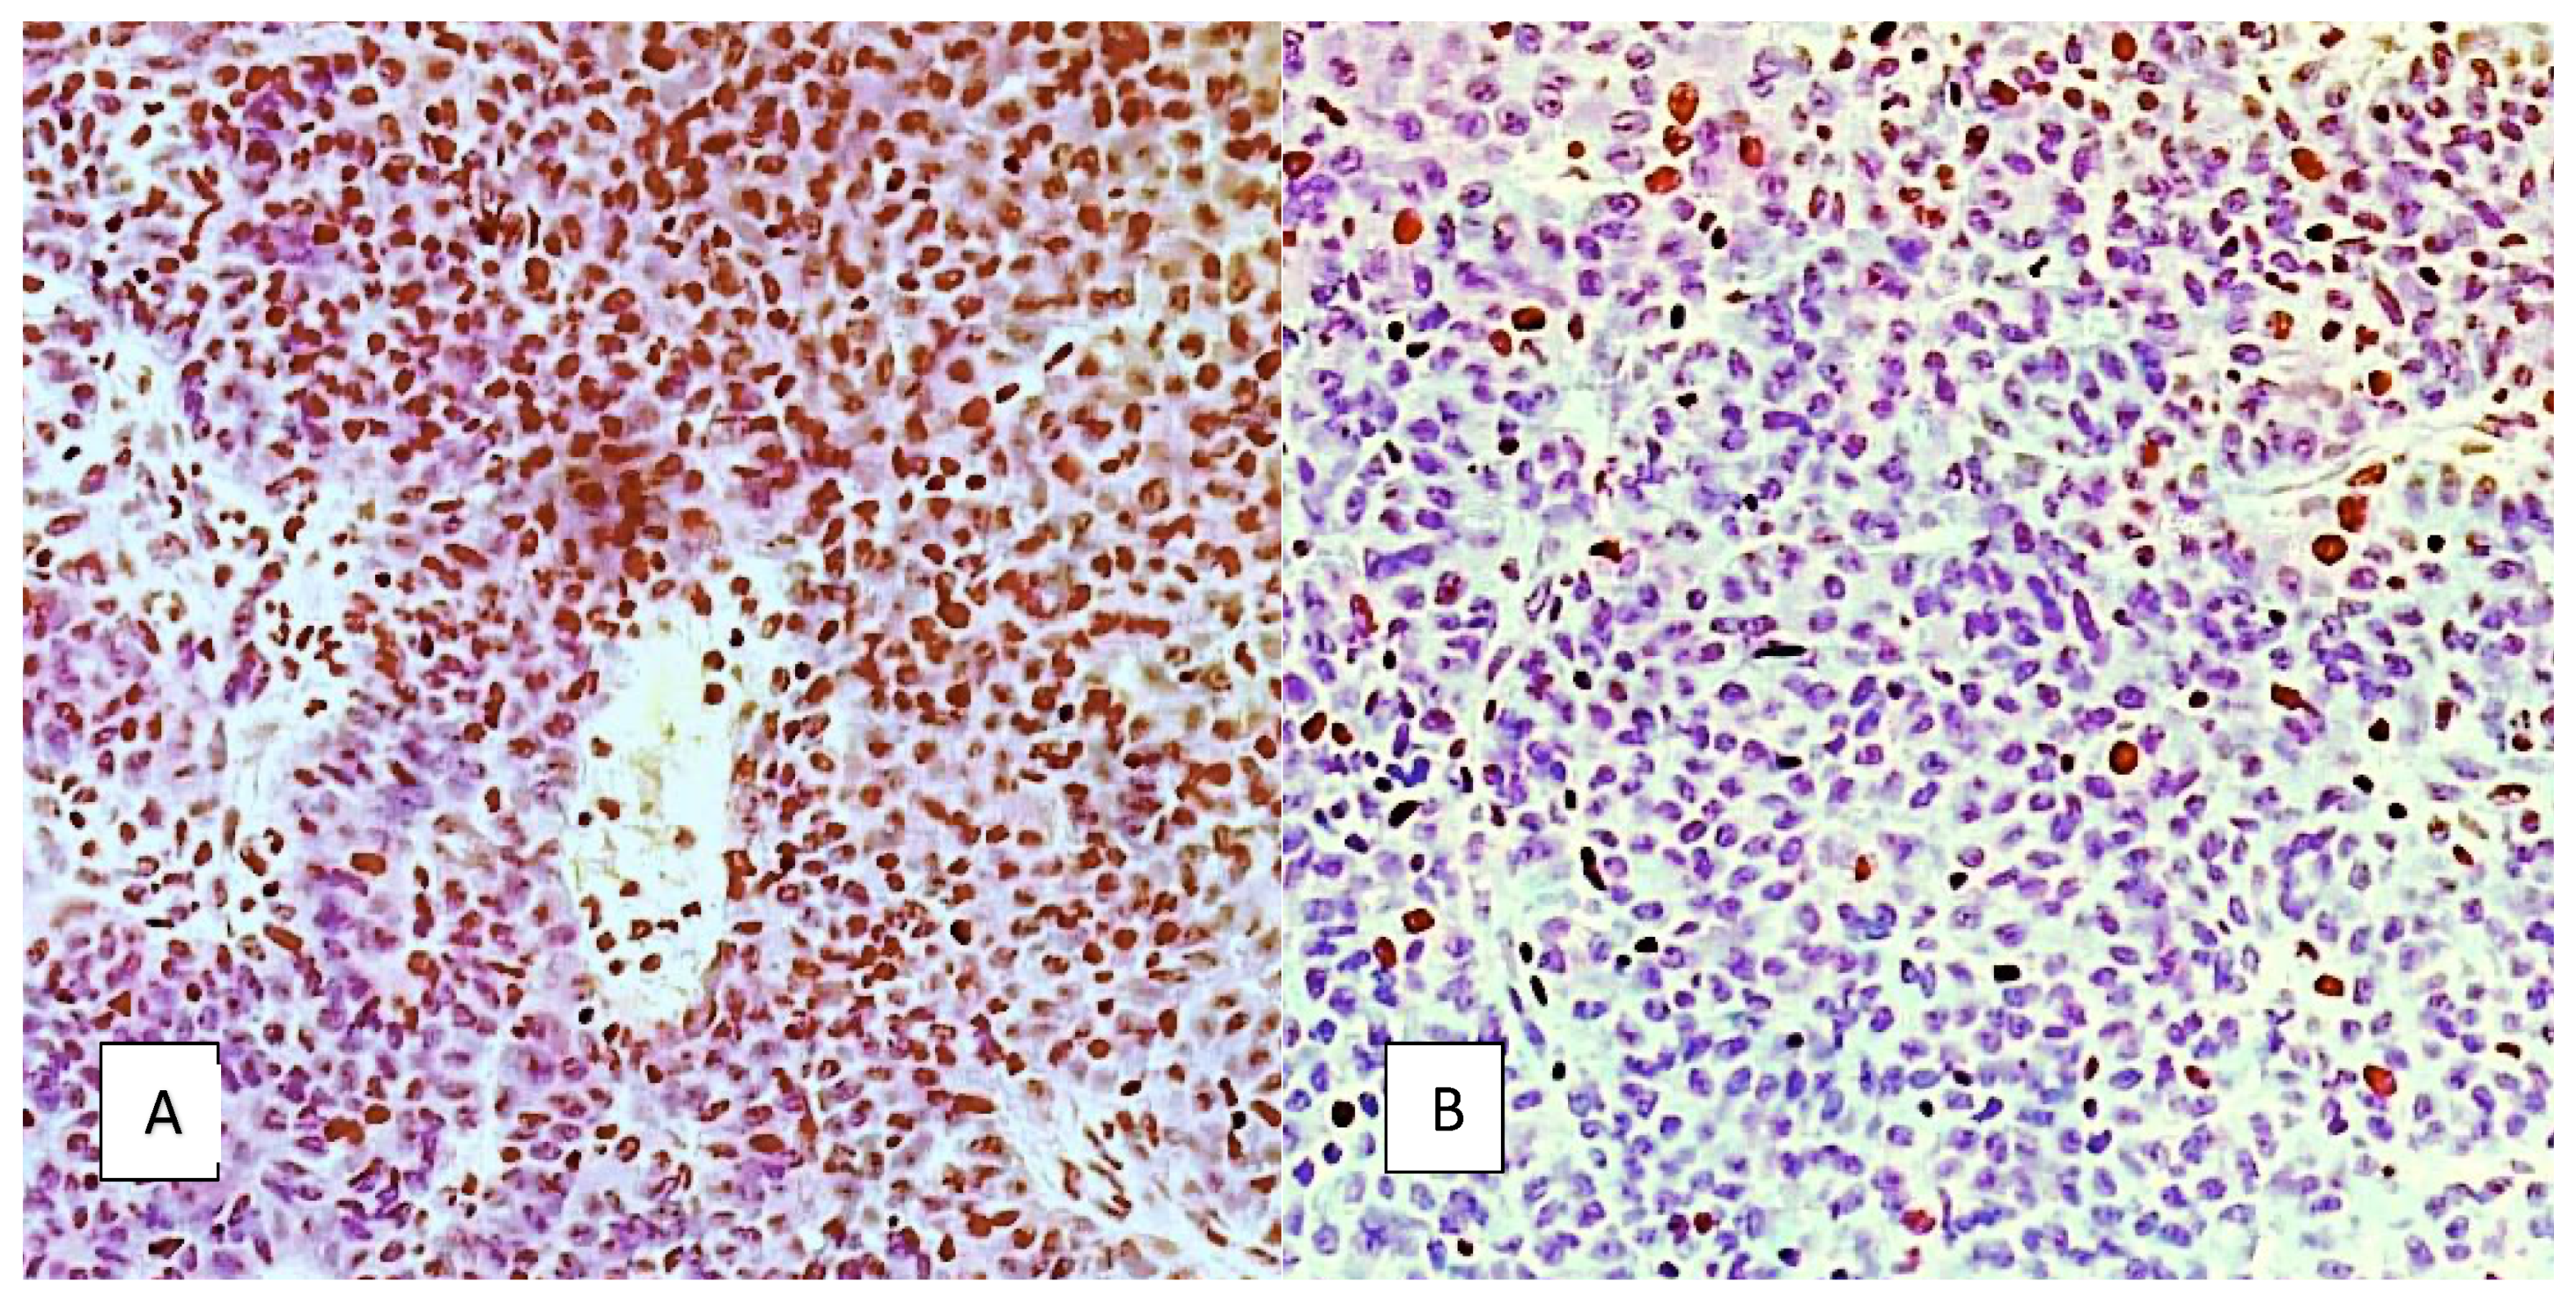

3.2. MRI DWI and DCE Parameters and Immunohistochemistry